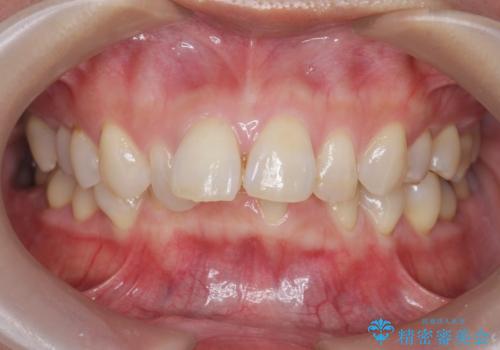

インビザラインで行う前歯のみの部分矯正

- 長年気になっていた前歯の歯並びを改善したいと、矯正治療を希望され思い切って来院されました。

費用と期間を相談し、「気になっているのは前歯だけ。」とのことでしたので前歯のがたつきのみをインビザラインで改善する矯正治療の計画を立てます。

しっかりとマウスピースの装用時間を守っていただき、非常にスムーズに治療を終了することができました。